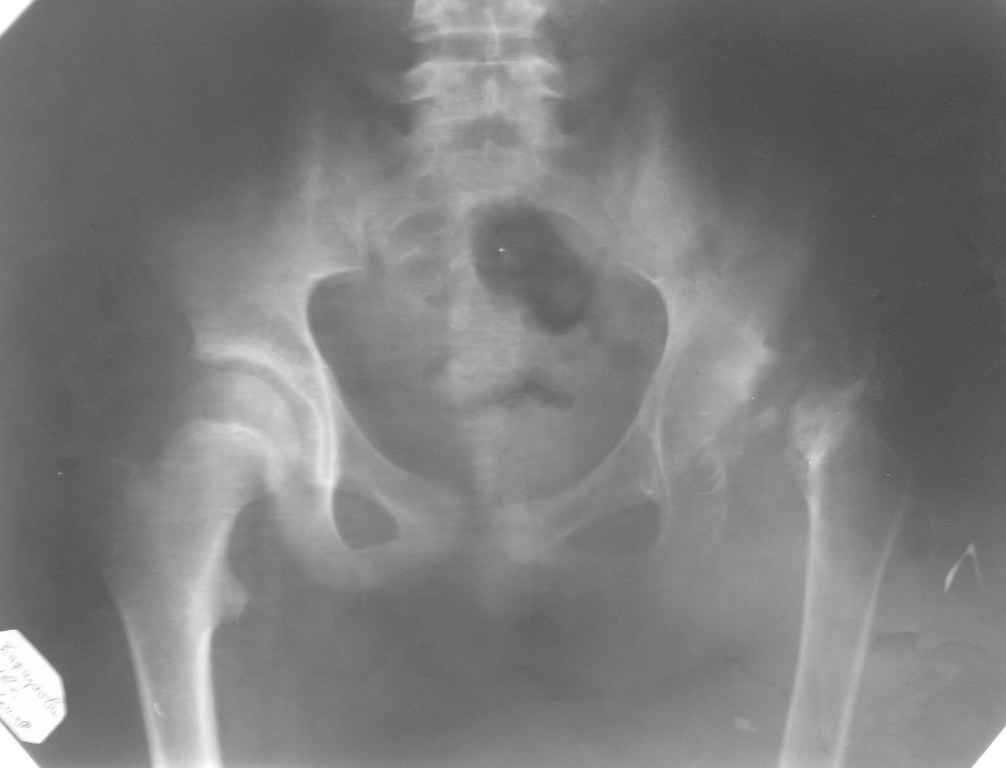

[Ortho] ассептический некроз головки левой бедренной кости

Снимок во вложении по поводу АНГБ